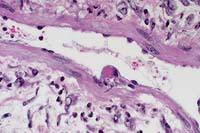

Case 22-3b. Skin. Note within the vessel, an endothelial cell bearing a large cytoplasmic pox inclusion. 40X

AFIP Diagnosis: Haired skin: Dermatitis, necrotizing, chronic-active, diffuse, severe, with ballooning degeneration, microvesiculation, necrotizing vasculitis, and numerous dermal and epidermal "sheep pox cells", Dorset cross, ovine.

Histologically, the skin lesions are characterized by dermal edema and cellularity with variable numbers of "sheep pox cells" - histiocytic-like cells with large vacuolated nuclei and poorly-defined eosinophilic cytoplasmic inclusions. In the lung there can be a necrotizing and proliferative bronchiolitis, often with "sheep pox cells" scattered throughout the proliferative zone.

Case 22-3a. Skin. Note ballooning degeneration of hyperplastic keratinocytes with eosinophilic pox inclusions in the cytoplasm. 20X